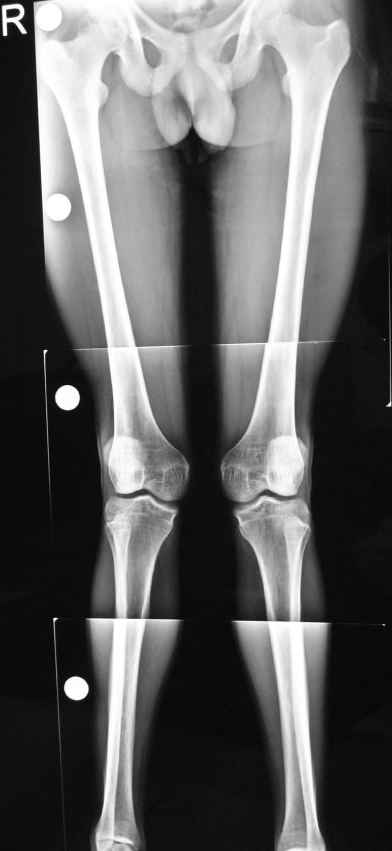

[Ortho] adult genu valgum

he is a 21 year old male short heighted thin built with failed

conservative treatment tried for ? post rcketic deformity in

childhood and teenage with bilateral genu valgum with intermalleolar

distance 14cm and no flat foot, the deformity is in the femur as it

fully corrects on flexion of the knee his main complaint is that his

knee knocks while walking and  pain in both knees while walking